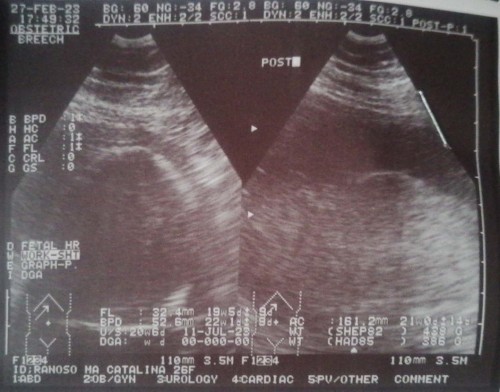

Hello po, ask lang po ano pong ultrasound yung pwedeng makita si baby kahit 2d lang. Yung pelvic ultz po kasi kapag naprint di ko nakikita si baby. 21 weeks here. Thank you po.

Consult mo muna sa OB mo kasi usually sa transV hindi na nirerequire ni OB kasi baka mamaya mag open cervix ka. Sa Pelvic Utz kitang kita naman sa akin @20 weeks nung pinatingnan namin ang gender nya. Anterior placenta pa ako sa lagay na yun. Ask mo bakit ganyan kalabo miii.

magpa CAS ka mommy. congenital Anomaly scan. next week pwede ka na 22-28weeks tinatanggap. pero depende sa clinic

TransV po Momsh mas malinaw or pwede na po ata kayo ng CAS ask po kayo sa OB niyo.